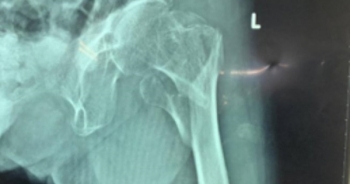

Nối các mảnh xương gãy cho cụ bà 101 tuổi

BV Chấn thương-Chỉnh hình TP HCM vừa nối lại thành công các mảnh xương gãy cho cụ bà 101 tuổi bị té ngã.